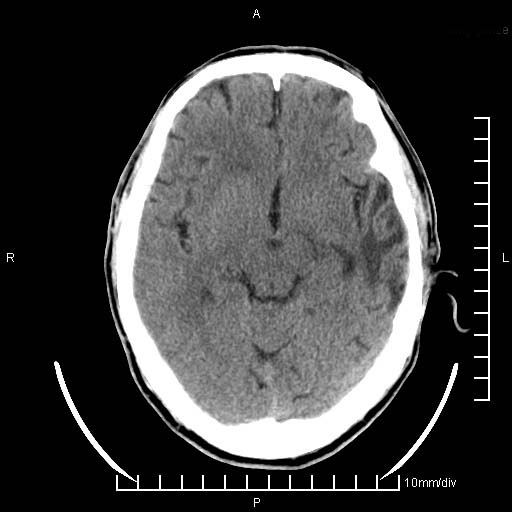

临床以双下肢浮肿,疼痛收治,无明显神经系统症状,既往无梗塞,出血病史。左颞叶见低密度灶,考虑什么?

考虑左侧颞叶脑软化灶。

无强化 无占位 软化灶吧

无强化、 无占位、局部脑沟增宽, 软化灶吧。